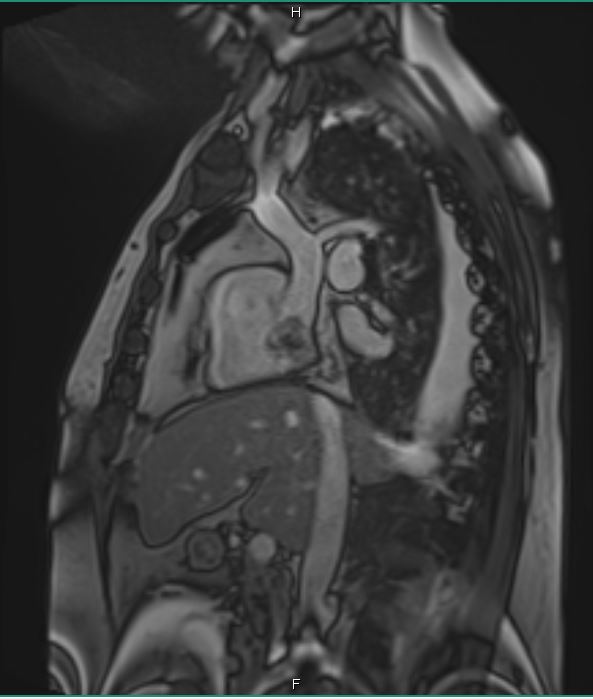

Cardiac MRI was performed on January 3, 2018, which revealed a large 2.5 × 2.9-cm lobular, fairly sessile mass in the right atrium. Without evidence of tissue destruction to suggest a malignant process, the lesion was suggestive of either myxoma or hematoma due to marked contrast uptake (which is seen less often with myxomas) (Figure 1).

Figures 1A-G. Cardiac MRI findings of a large, lobular, fairly sessile mass in the right atrium, measuring 2.5 x 2.9 cm, suggestive of either myxoma or hemangioma.